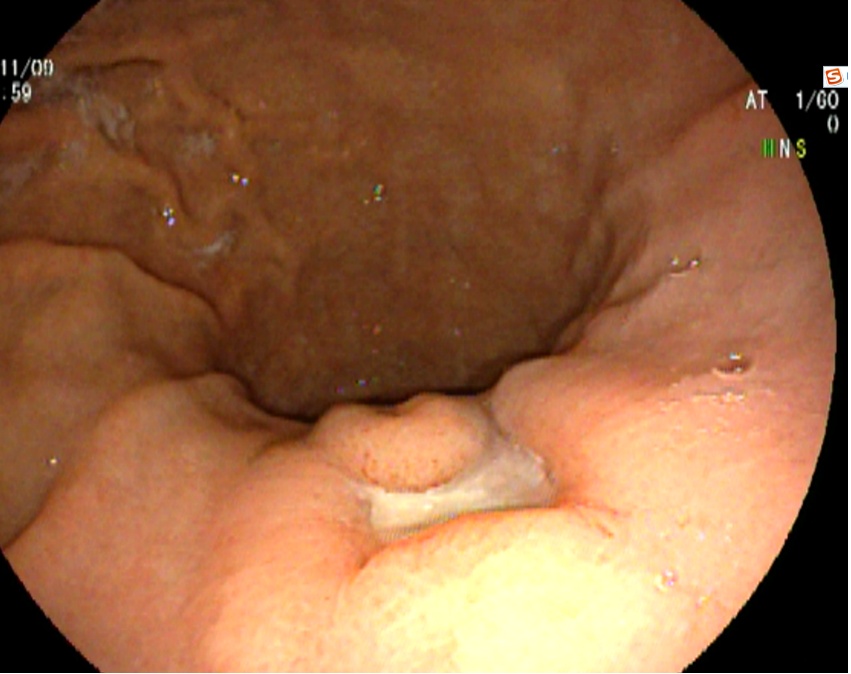

病房收治一名女性患者,68岁

患者主诉:阵发性上腹痛半月余

门诊行无痛胃镜,慢性浅表——萎缩性胃炎,胃石形成,建议内镜下治疗。

治疗效果

兰索拉唑抑酸1周(30mg bid)和碳酸氢钠片口服1周(600mg tid),补液支持。

一周后镜下复查,胃石消除。